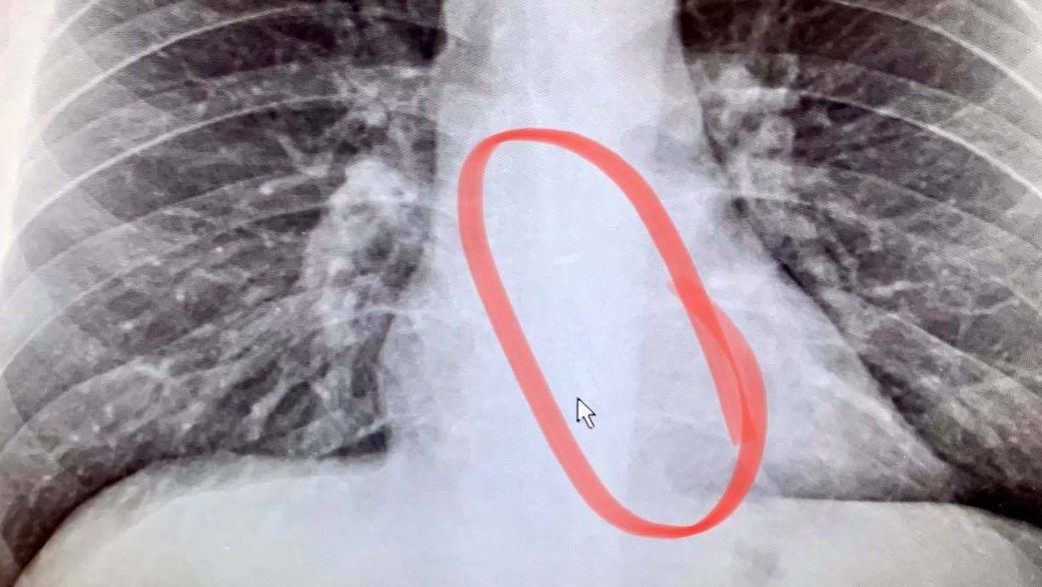

לצד אי הנעימות, ברדפורד הבחין שאחת האוזניות שלו הלכה לאיבוד; משפחתו התבדחה שאולי הוא "בלע אותן", אבל הוא הרגיש שזה צירוף מקרים מוזר מדי. ואכן, נסיעה לחדר המיון הובילה לצילום רנטגן של החזה שלו, שם התגלתה אחת האוזניות ממש במרכז הושט. האוזניה הסוררת הוצאה מהגרון במהלך הליך ניתוחי פשוט ולא פולשני, שבסופו חזר גוטייר לביתו. "הרופא אמר שזה נדיר מאוד שחסימה כזו לא כואבת או יוצרת אי נוחות קיצונית. לא חשבתי על זה בכלל שללכת לישון עם האוזניות עשוי להיות סיכון בריאותי. היה לי הרבה מזל".